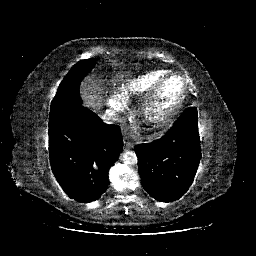

Original NATIVE CT scan (input)

No window - Raw intensity values

Lung window (WL -600, WW 1500 β†’ Low βˆ’1350, High +150)

Mediastinum window (WL 40, WW 400 β†’ Low βˆ’160, High +240)